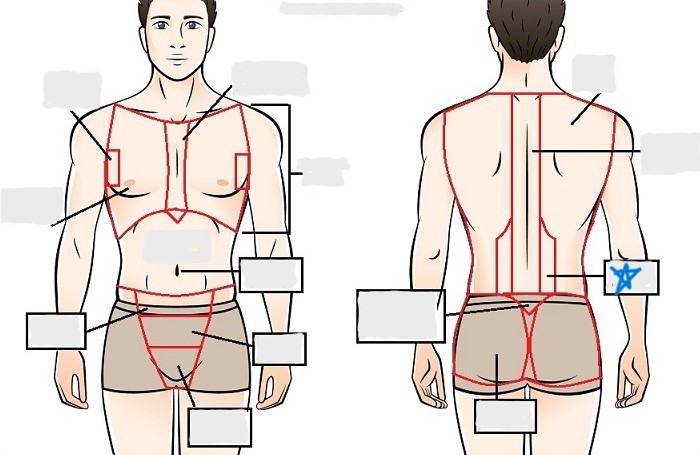

axial

cephalic

occipital

frontal

otic

orbital

nasal

oral

mental

cervical

dorsal

scapular

vertebral

lumbar

sacral

gluteal

thoracic

sternal

mammary

axillary

abdominal

umbilical

pelvic

inguinal

pubic

perineal

appendicular

acromial

brachial

antecubital

olecranal

antebrachial

carpal

manus

coxal

femoral

patellar

popliteal

crural

sural

peroneal

calcaneal

plantar